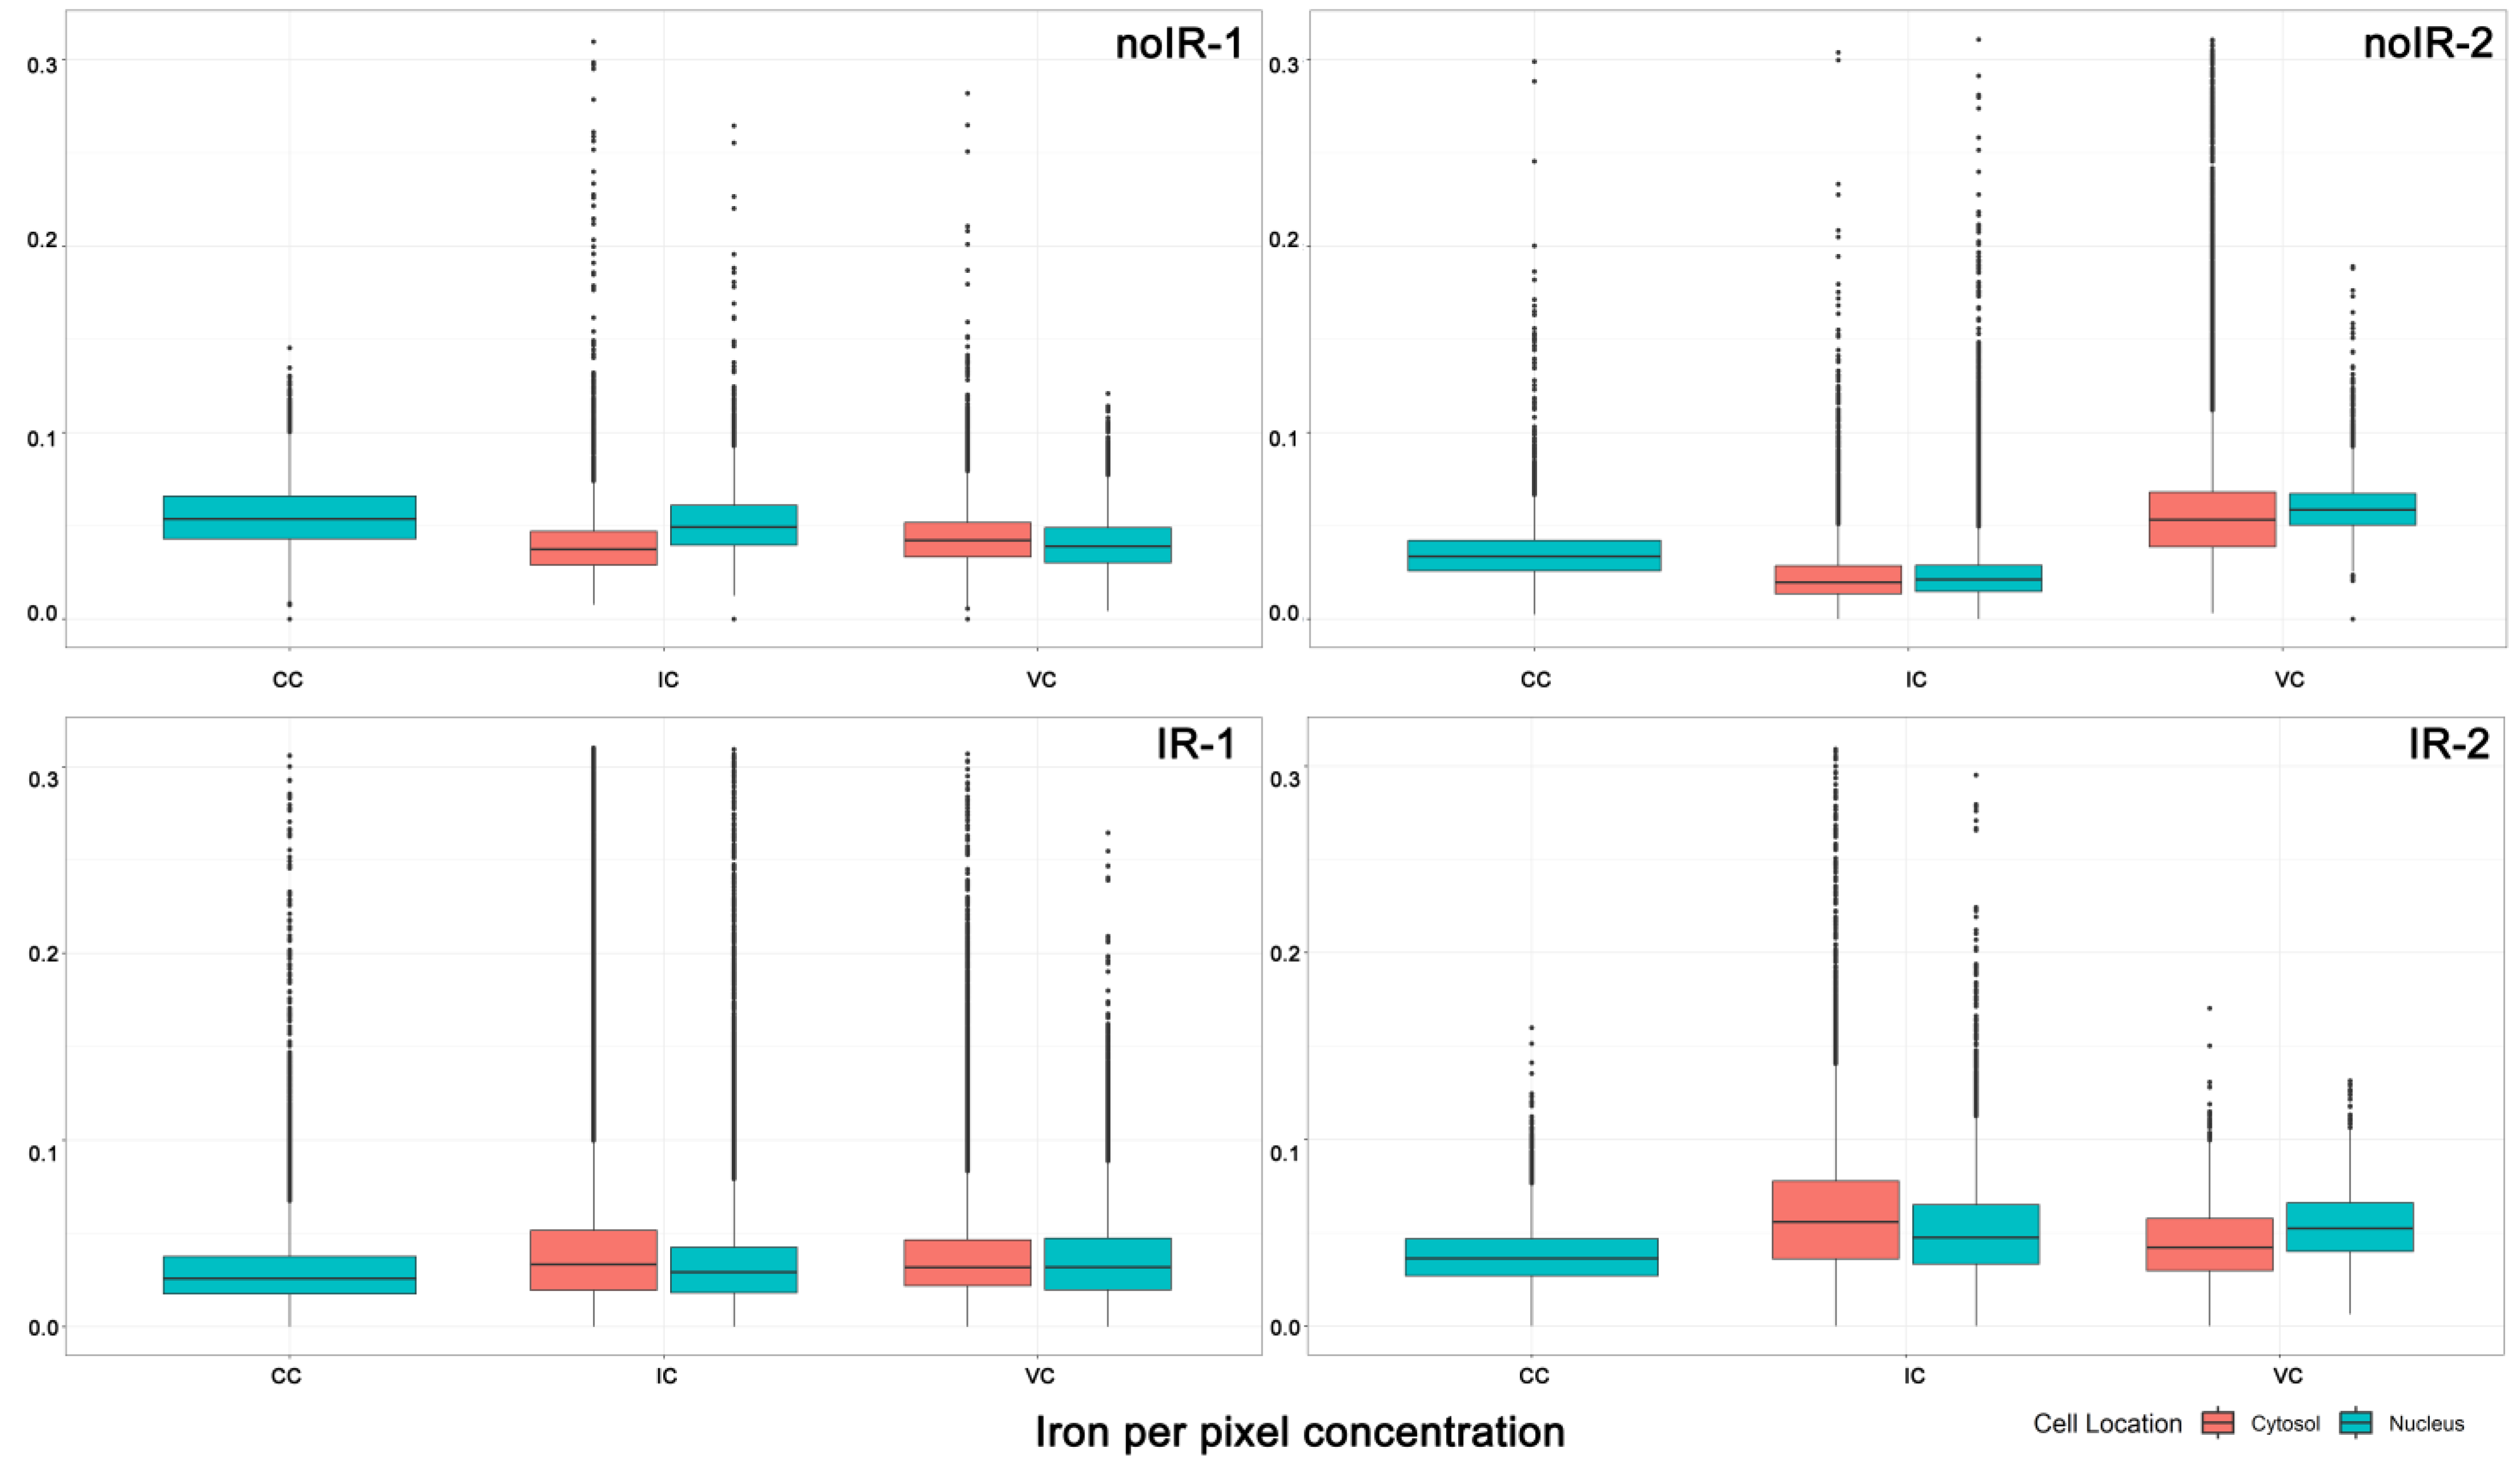

2.2. Statistical Analyses of ROI Data Extracted from XFM Images

2.2.1. Mean Pixel Concentration Analysis—Cell Type Analyses

2.2.2. Mean Pixel Concentration Analysis—Individual Cell Analyses

2.2.3. ANOVA Evaluation of Cell-to-Cell Elemental Differences

2.2.4. T-Test Evaluation of Differences between Different Scans of the Same Cells

2.2.5. Tissue Region Analyses